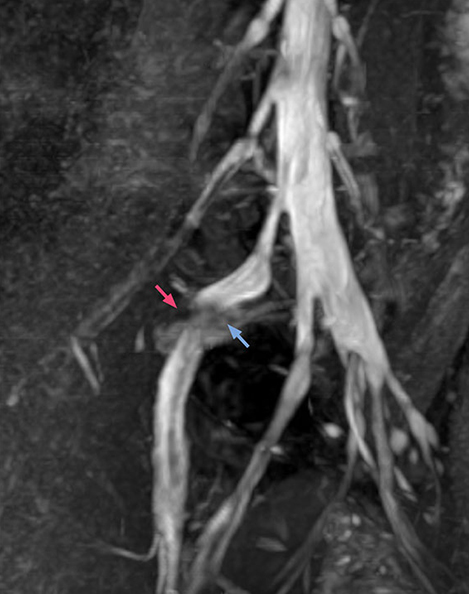

“In patients with lower extremity neurological symptoms, NerveVIEW helps us to determine the disease matching the patient’s symptoms by directly visualizing the nerves. We use the sequence mainly, when there is suspicion of intraforaminal stenosis, extraforaminal stenosis or lateral disc herniation, which is often based on routine T2- and T1-weighted images. Additionally, the excellent depiction of the course of nerves makes NerveVIEW a good navigator when applying treatment such as block therapy or surgery.”

“In such case, we would then browse through axial T2-weighted MR images slice by slice and mentally reconstruct the actual situation based on both radiculography and MRI. Fortunately, NerveVIEW can now very well show nerve courses and presence of nerve compression or edema in one single image series.” “We have often seen NerveVIEW directly depict details of the nerve compression that were not observed by radiculography. Therefore, we think that with NerveVIEW we can reduce the number of invasive examinations, especially for some patients with lumbar plexus symptoms.”

The key concept in MR neurography, Dr. Yabuki stresses, is the ability to directly visualize spinal nerves, versus inferring the presence of pathology indirectly. “Before NerveVIEW, we estimated compression of the nerve by looking for the presence or absence of fat signal on other MR images,” he says.

“For example, in sagittal images, when the presence of fat is observed in the intervertebral foramen, it suggests that there is a margin around the nerve. Similarly, the absence of fat indicates that the nerve is being compressed. So, we used to deduce nerve compression indirectly. With NerveVIEW, however, we can observe the condition of the nerves directly, regardless of the presence or absence of fat. We always prefer such direct observation of anatomy over having to make an inference about it.”

“Although symptoms of typical disc herniation and atypical hernia are very similar, the actual site of herniation is different. It is therefore important to characterize the nerve’s condition both inside and outside of the intervertebral foramina. “Conversely, if we see no abnormality in NerveVIEW, we can assume at least that there is no severe condition that requires surgery. Like this, it can help us avoid unnecessary surgery. NerveVIEW can have a tremendous impact in this way.”

“The intra-luminal signal of veins, especially around the intervertebral space, can be suppressed well with NerveVIEW. As a result, we can easily observe the detailed nerve structure around the posterior ganglion,” he says. “This is why we use 3D NerveVIEW for intraforaminal stenosis and extraforaminal stenosis/herniation (lateral disc herniation). On the other hand, if herniation is suspected to exist inside the dorsal root ganglion (DRG), balanced TFE or ProSet-FFE is applied. NerveVIEW is not suitable for evaluating the median type of herniation.” The SE-EPI DWI-based method for MR neurography works well for large FOV exams like whole-body MRI, but focal examination of nerves is often limited by the attainable spatial resolution (both inplane and slice direction) and geometric distortion. “3D NerveVIEW achieves higher in-plane resolution – close to our other routine spine sequences – and the source images can be used instead of adding a fat-suppressed T2-weighted sequence,” Tanji says.

According to Tanji, methods such as ProSet FFE, STIR or 3D VISTA are anatomically nonselective because background signals, for instance from blood vessels, often interfere with nerves, which hampers evaluation of details, especially at the peripheral side of the nerves.

“NerveVIEW can clearly show nerve courses and presence of nerve compression. However, when multiple abnormalities are seen, it can still be hard to determine which nerve is causing the symptoms,” says Dr. Yabuki. “In our experience so far, we see abnormal findings on NerveVIEW in about 70% of elderly patients. As the pain is usually caused by only one nerve, we thus need to find the exact corresponding nerve.” “With a nerve root block, the patient's pain is improved by infiltration of local anesthesia directly around the nerve root considered to be responsible. Knowing such nerve root block findings prior to image interpretation, helps to easily recognize abnormal findings on NerveVIEW as well. In other words, without a priori knowledge, based on symptoms and/or nerve root block findings, we must be aware of the possibility of overdiagnosis.”